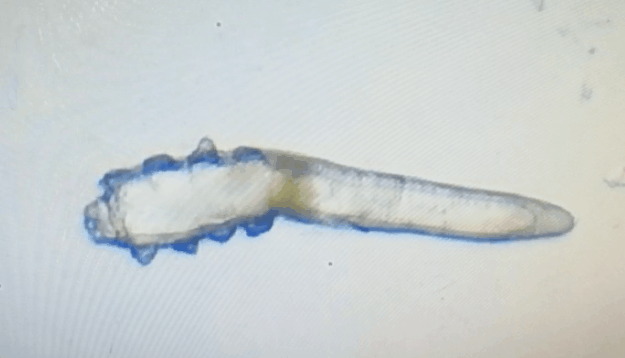

廈門(mén)眼科中心眼表及角膜病專(zhuān)家商旭敏博士指出:蠕形螨中的毛囊蠕形螨和皮脂蠕形螨可寄居于人體。在眼部,毛囊蠕形螨常寄居于睫毛囊,而皮脂蠕形螨多寄居于眼瞼皮膚的皮脂腺和瞼板腺。蠕形螨瞼緣炎是蠕形螨感染瞼緣所致的慢性炎性反應(yīng)性疾病,主要累及瞼緣皮膚、睫毛囊和腺體以及瞼板腺,以眼癢、眼異物感、眼干、瞼緣充血、鱗屑及睫毛根部袖套狀分泌物等為典型臨床表現(xiàn),嚴(yán)重者可引起結(jié)膜及角膜并發(fā)癥,該病可能具有一定的傳染性。

蠕形螨會(huì)引起睫毛異常,引發(fā)瞼緣炎性反應(yīng),瞼板腺堵塞,引起結(jié)膜炎、角膜炎等并發(fā)癥,嚴(yán)重的話將發(fā)生角膜穿孔致視力損傷甚至失明。